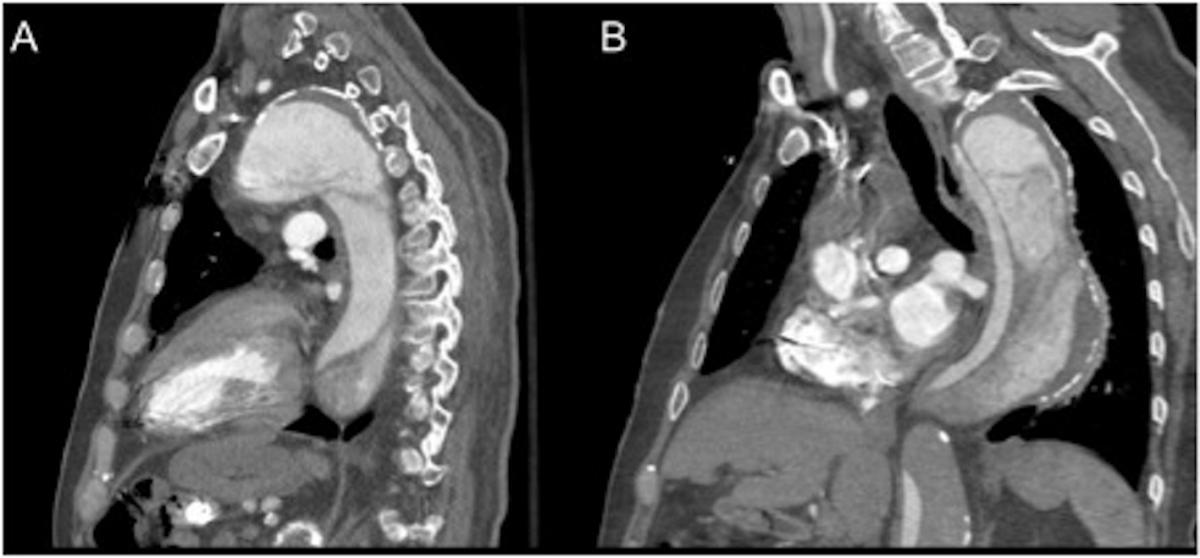

A 60-year-old male presented with chest pain, underwent a CT angiogram in the emergency department, demonstrating a 6.5 cm proximal ascending and transverse aorta and 7.5 cm descending aorta due to chronic aortic dissection (Figure 1,2). His medical co-morbidities included hypertension, previous stroke, coronary artery disease, sick sinus syndrome, cardiomyopathy, and dyslipidemia. His surgical history was positive for four open-heart operations, including: aortic valve replacement, Bentall- Cabrol operation for type A dissection, reoperation for delayed hemorrhage from suture-line pseudoaneurysm, and coronary artery bypass grafting.

This extensive surgical history turned out to be life-saving for this patient. The preoperative CT scan also showed a contained rupture of an ascending pseudoaneurysm into the retro-aortic space (Figure 1C). Given his extensive adhesions, he did not develop frank rupture or tamponade physiology and the area of extravasation was contained by previous adhesions.

Figure 1: CT angiogram showing the thoracic aortic aneurysm. A: Aortic arch aneurysm with contrast enhanced true lumen surrounded by thrombus. B: Aortic arch with proximal septum. C: ascending aorta with contained rupture of a pseudoaneurysm in the retro-aortic space. D: Infrarenal abdominal aortic dissection with clotted false lumen.